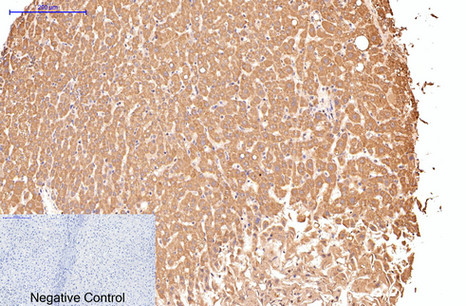

- Immunohistochemistry analysis of paraffin-embedded Human liver tissue using CD16 antibody.High-pressure and temperature Sodium Citrate pH 6.0 was used for antigen retrieval.Negative control was used by secondary antibody only.